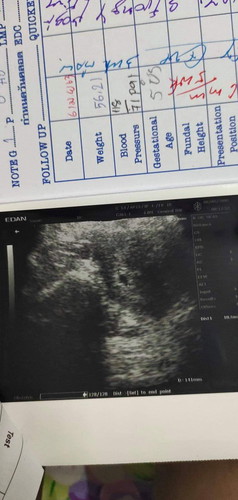

พึ่งตั้งครรภ์ได้ 5สัปดาห์ค่ะ แต่กังวลว่าปกติมั้ย ยังไม่เห็นตัวเด็ก และถุงน้ำคร่ำเล็กไปมั้ย ใครรู้ แนะนำหน่อยนะค่ะ

เราเจอน้องตอน 8w ค่ะ อย่าเพิ่งกังวลนะคะ ☺️

บ้านนี้เจอตอน 8 สัปห์ดาค่ะ